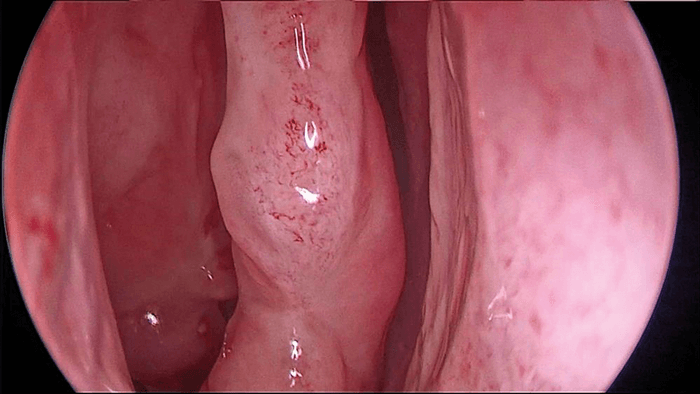

Figure 1a. View of the middle turbinate without contrast enhancement (KARL STORZ IMAGE1 S™).

Figure 1b. View of the middle turbinate with and middle meatus

with Chroma contrast enhancement with the KARL STORZ IMAGE1 S™.

in imaging lie especially in new visualisation tools, computer-assisted navigation and imaging of the brain and neurovascular structures and 3D endoscopy has been developed to visualise anatomic structures in three dimensions. This should help to get a better impression of the depth and focus on structures, especially neurovascular structures like the carotid artery. With digital enhancement of contrast or fluorescent dyes to help impregnate different tissues, intraoperative differentiation of healthy tissue vs. tumours is facilitated (see Figure 1a and 1b). Novel instrumentation with remotely controlled malleable shafts for endoscopes and instruments that can be directed around the corner or around structures like vessels are currently developed.